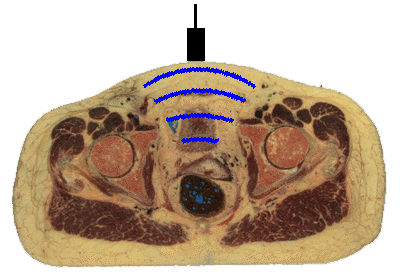

Ultrasound (US) uses high-frequency sound waves for scanning body regions. Ultrasonography is a non-invasive technique that does not use x-rays, so it is safe for any patient. US is commonly utilized for prenatal diagnosis for this reason. To perform US, a transducer generates a focused beam of sound waves that is directed toward the body region to be studied. The sound beam is oriented in a specific plane, such as sagittal (longitudinal) or axial (transverse). The transducer is moved across the external body surface while the image appears on a monitor.

The sound beam srikes body structures that echo (reflect) the sound waves to varying degrees--tissues have different acoustic impedances. The reflected sound waves are detected by the transducer and converted to a series of electrical impulses that is computed to form an image viewed on a screen. Selected views can be captured on film. However, the real advantage of US is the ability to move the transducer in real time and see what is happening. Movement can be detected, such as the beating of a fetal heart. A video can be made of the images to record the movement. Ultrasonographic images are not sharp, but "fuzzy" and require skill in interpretation. A single image is not as useful as a real time exam.

The image displayed on the monitor depends upon the echogenicity of the structures beneath the beam. Fluids are echolucent, so the bladder and the gallbladder appear dark. Solid organs and soft tissues are echogenic. Structures with calcium are very echogenic. A gallstone appears bright with US. Bone is so dense to sound waves that it cannot be evaluated. This puts the brain and spinal cord "off limits" for US examination. US is most suited to study of heart with its valves (which move), gallbladder, vessels (to check for thrombi and flow), and internal genitalia.

Movement can be further enhanced by "doppler" ultrasonography in which flow away from the transducer is converted to a signal that appears blue, while flow toward the transducer appears reddish. This can be useful in recording flow in arteries and veins.